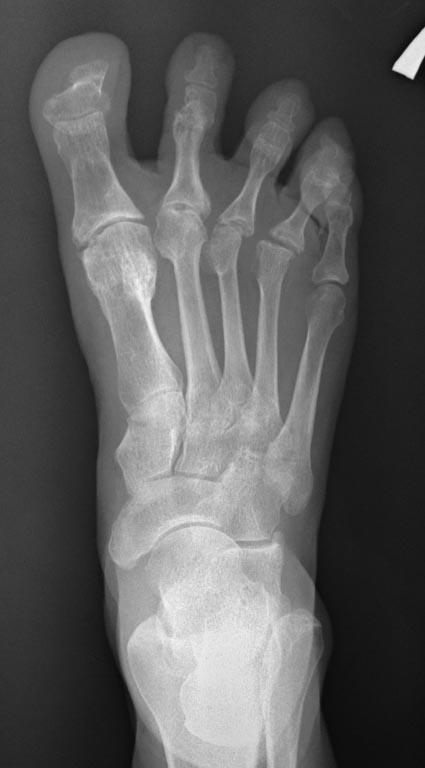

Пциентка Н, 58 лет. Больна с 2005г. Лечилась консервативно. Со слов,

тогда было сильное искривление 1,2,3,4 пальцев в латеральную сторону.

В 2012г. операция: коррекция деформаций 1,2,3, 4 пальцев.Рецидив.

В 2013г. коррекция деформации 2,3,4 пальцев. С ноября

2014г. рецидив деформации 1,2,3,4 пальцев.

Возможные варианты коррекции?